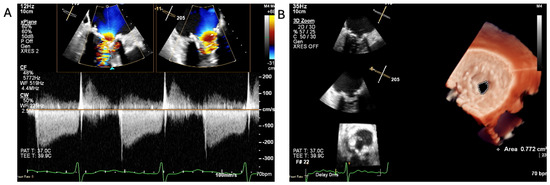

1.1.3. Case 3

2.3. The Saga of Relapsing IE of the Prosthetic Mitral Valve Causing Structural Valve Degeneration and Transcutaneous MViV Prosthesis